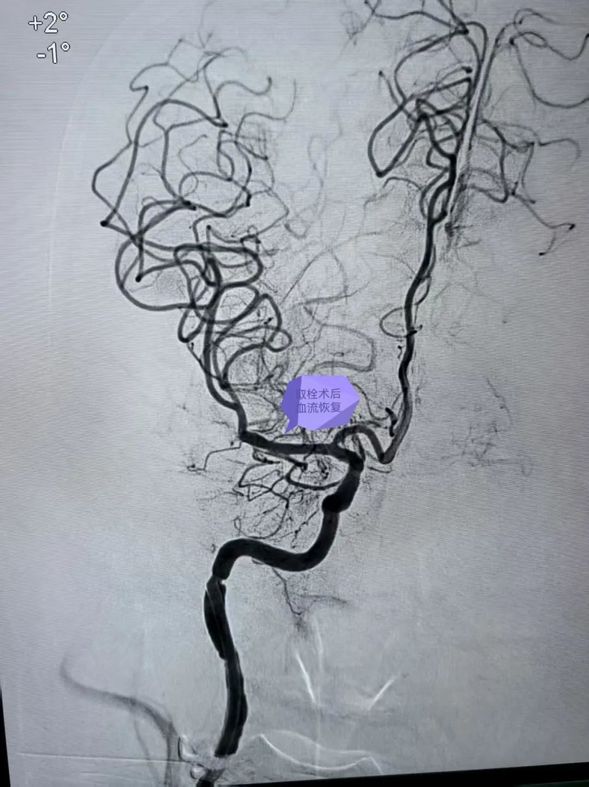

取栓后血流恢复